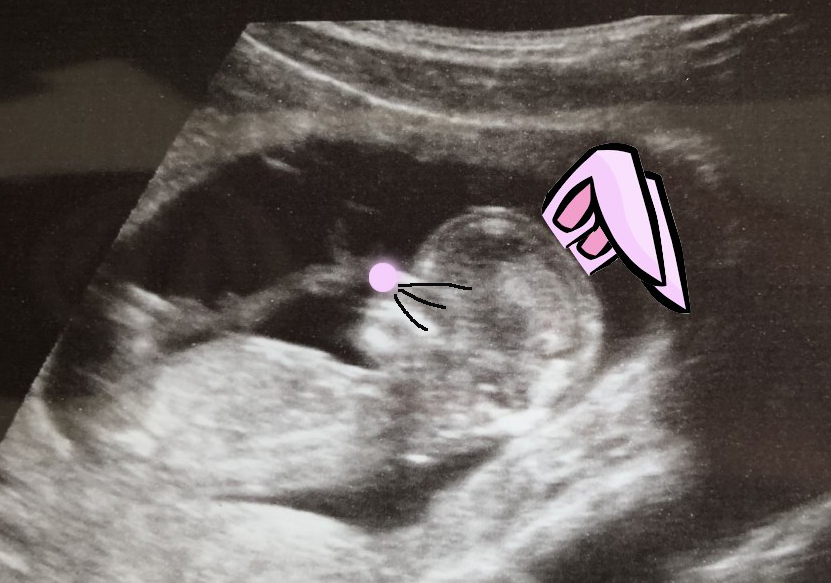

Happy Easter from the oven!

Frosty needs to start getting familiar with their parents being two true brighella, hence this first innocent joke we did to wish everyone a happy Easter:

Frosty is practicing lots of stuff they’ll start performing the moment they’ll get out of the oven, such as breathing, sucking, facial expressions, libs mobility. We saw the little tornado in action earlier during the routine scan, so there is no doubt they’re doing their homework already.